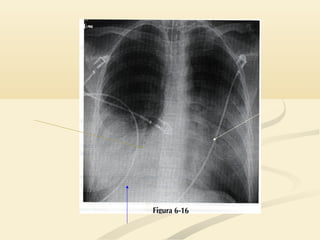

OJO!!!!!OJO!!!!!  El signode la silueta puede ser engañoso en una placa pocoEl signo de la silueta puede ser engañoso en una placa poco penetrada.penetrada.  Si no puedes ver la columna a través del corazón, la placa tieneSi no puedes ver la columna a través del corazón, la placa tiene una penetración insuficiente y el signo de la silueta puede induciruna penetración insuficiente y el signo de la silueta puede inducir a error.a error.  El borde cardíaco derecho se superpone a la columna y no haceEl borde cardíaco derecho se superpone a la columna y no hace prominencia en el pulmón derecho; la densidad de hueso de laprominencia en el pulmón derecho; la densidad de hueso de la columna oculta la interfase pulmón/corazóncolumna oculta la interfase pulmón/corazón

 Si no puedes ver la columna a través del corazón, la placa tieneSi no puedes ver la columna a través del corazón, la placa tiene

una penetración insuficiente y el signo de la silueta puede induciruna penetración insuficiente y el signo de la silueta puede inducir

a error.a error.

 El borde cardíaco derecho se superpone a la columna y no haceEl borde cardíaco derecho se superpone a la columna y no hace

prominencia en el pulmón derecho; la densidad de hueso de laprominencia en el pulmón derecho; la densidad de hueso de la

columna oculta la interfase pulmón/corazóncolumna oculta la interfase pulmón/corazón